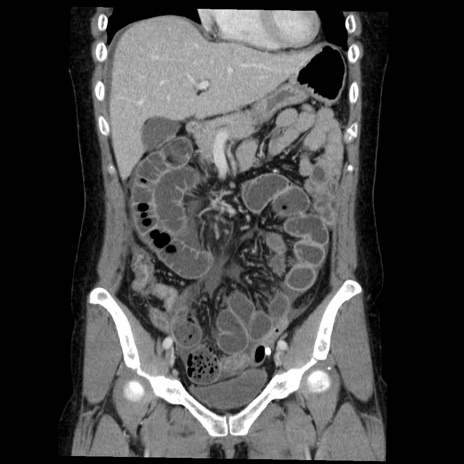

横断像

症例6(冠状断像)

【症例】50歳代女性

【既往歴】卵巣癌術後(8年前に当院で卵巣摘出)